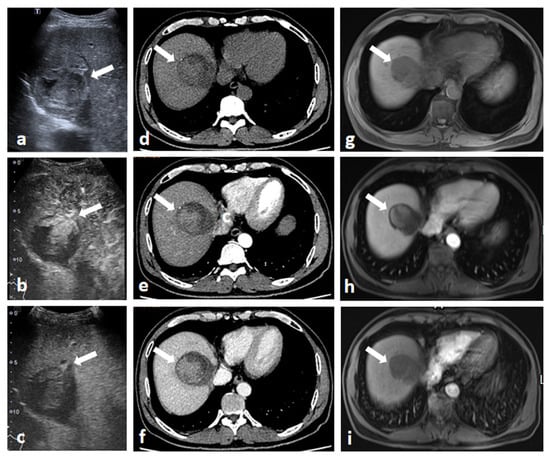

3.2. CEUS LI-RADS Features between Different Nodule Characteristics and Liver Background

3.3. Comparison between CEUS and CT/MRI on LI-RADS Major Features for Recurrent HCC

3.4. Optimal Diagnosis Algorithms on CEUS, CT and MRI for Diagnosing Recurrent HCC